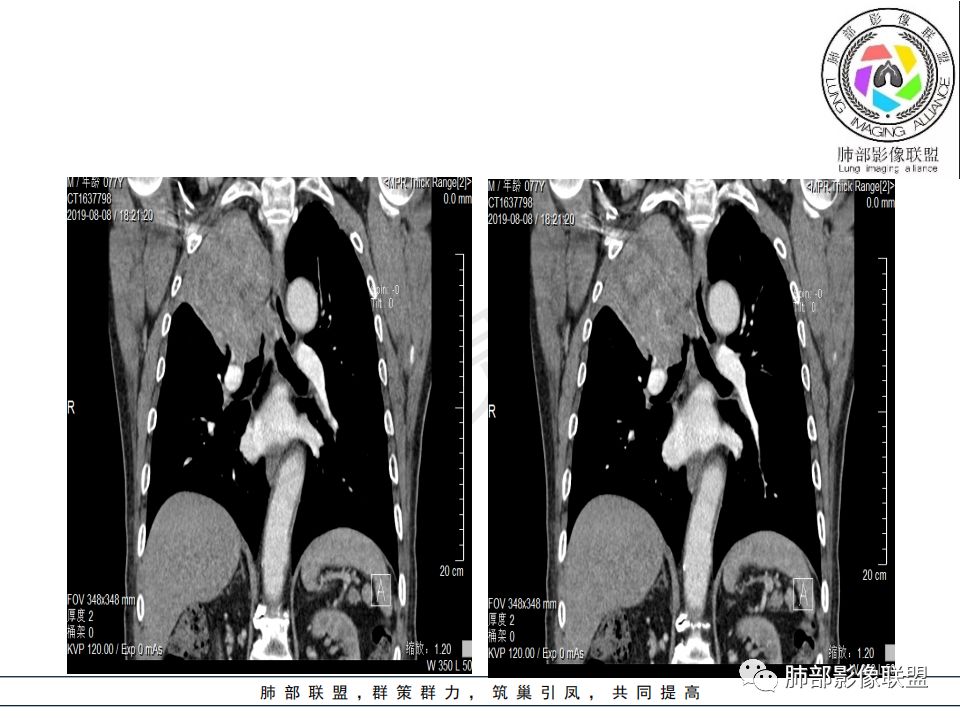

影像:影像右侧大支气管阻塞,临床没有症状或很轻微,要想到胃腺癌转移;胸壁代偿好,透亮度稍低不明显,慢性过程;34.8-52.5HU,主病灶支气管前壁另有1结节,都做成增强两期了,动脉期较平扫有强化;

右肺上叶肿块,边缘光滑,略膨隆,近段支气管堵塞,平扫密度均匀,增强后不均匀强化,其内可见不规则血管和坏死,纵隔淋巴结肿大,老年男性,无感染性病史,综合考虑恶性肿瘤(鳞癌,腺癌),鉴别:OP(一般下叶多见)

从强化情况和冠状位看主要还是从外向内的一个肿块,有不张,但不张范围不大,近端支气管堵塞,考虑腺癌或类癌(原发或转移都可能),鉴别鳞癌。

@曹坤,河北保定清苑区人民医院ct室 肿块大,阻塞和不张范围小,强化这么大肿块没有明显坏死,鳞癌这样相对少见了

@刘鋆(福州长乐区医院)影像科 转移啊,腔外都在生长,部分通过支气管壁进入腔内

@刘鋆(福州长乐区医院)影像科 先转移生长到外面,然后进入腔内生长,也是外朝内一种,与平时那种外朝内生长逐渐侵犯近端气管没有太多区别,只不过这个是转移而已。

1.右肺上叶较大块影,密度不均,轻度强化并见低密度区,所属支气管截断并腔内突入,是符合肺鳞癌的影像学特征和生物学行为的。